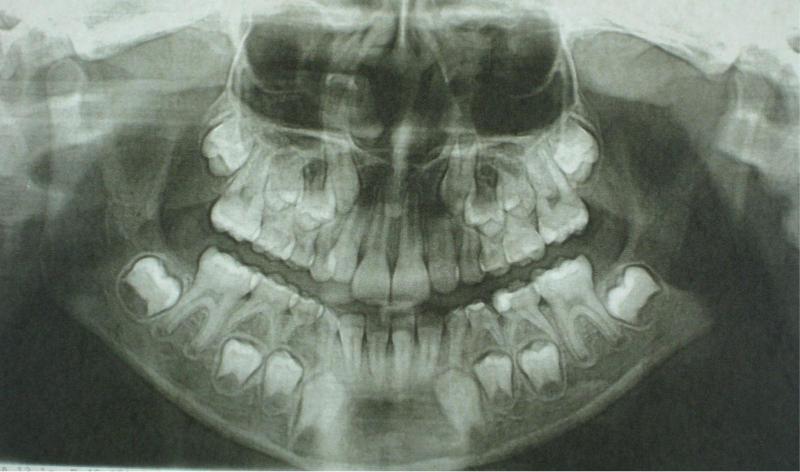

Фотографии и схемы для ОПТГ и мезиального прикуса